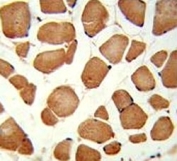

IHC analysis of FFPE human skeletal muscle stained with ANGPTL4 antibody

IHC (Paraffin) : 1:50-1:100